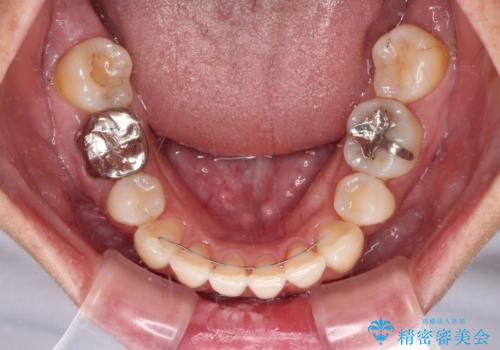

八重歯で口元が膨れている ワイヤー装置での抜歯矯正

- 八重歯と、それによる口元の膨らみを気にして来院された患者様です。

八重歯・デコボコの解消とともに、前方に張り出した上顎前歯を引っ込めることを目的とし、上下左右の第一小臼歯4歯を抜歯をしてワイヤー矯正により治療することとしました。

半年もしないうちに八重歯は解消し、治療も当初予定通り2年強で終えることができました。